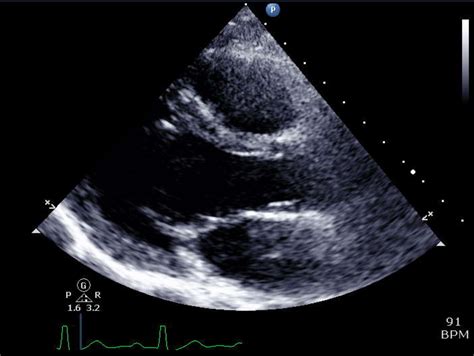

An echocardiogram, often referred to as an echo, is a type of ultrasound test that uses sound waves to create images of the heart. These images help doctors assess the heart’s size, shape, and function. Echocardiograms are non-invasive and painless, making them a preferred method for diagnosing various heart conditions.

A normal vs abnormal echocardiogram can reveal significant differences in heart health. In a normal echocardiogram, the following findings are typically observed:

• Heart Size and Shape: The heart appears normal in size and shape, with no signs of enlargement or deformation.

• Valve Function: All heart valves (mitral, tricuspid, aortic, and pulmonary) open and close properly, allowing for smooth blood flow.

• Chamber Function: The heart’s chambers contract and relax normally, indicating efficient pumping action.

• Blood Flow: Blood flows smoothly through the heart and major blood vessels, with no signs of obstruction or leakage.